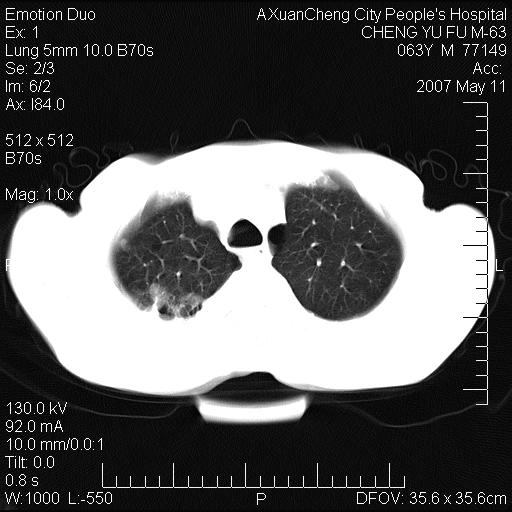

以下是引用小初学者在2007-5-11 19:32:00的发言:[br]1、首先考虑干酪性肺炎支气管播散[br]2、支气管肺泡癌待排

以下是引用zhangzhongshou在2007-5-11 19:30:00的发言:[br]细支气管肺泡癌可能性大。